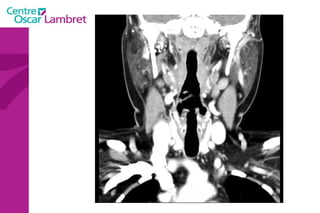

Les  artères Carotides Communes  : La droite vient du TABC. La gauche vient de la crosse de l’aorte. Elles n’ont aucune branche collatérale. L’appareil circulatoire

L’artère carotide primitive droite : Elle naît à 3 cm en arrière de l'articulation sterno-claviculaire à la hauteur de T1. monte dans la gouttière carotidienne le long de la trachée et du corps thyroïdien, de l'oesophage puis du larynx et du pharynx.  Elle s’évase avant sa terminaison en regard du bord supérieur du cartilage thyroïde et de C4.  L’appareil circulatoire

L’artère carotide primitive gauche  : naît directement de la crosse aortique et comporte un premier segment intra thoracique en arrière du manubrium sternal. Son segment cervical est identique à celui de la carotide primitive droite.  L’appareil circulatoire